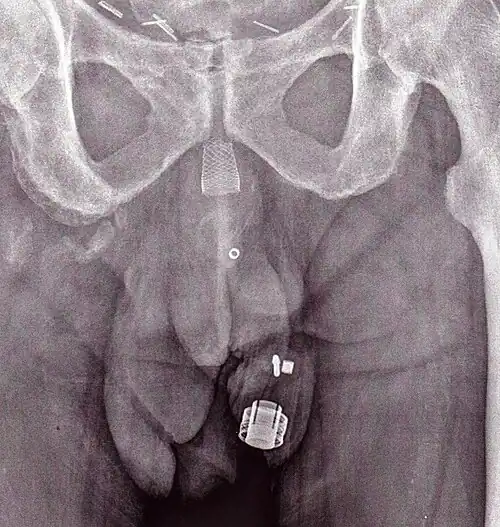

Uma imagem de raio X de um ZSI 375 implantado. O aparelho está desativado - a mole está comprimida abaixo do topo do cilinder. O paciente está continente.

Uma imagem de raio X de um ZSI 375 implantado. O aparelho está desativado - a mole está comprimida abaixo do topo do cilinder. O paciente está continente. -